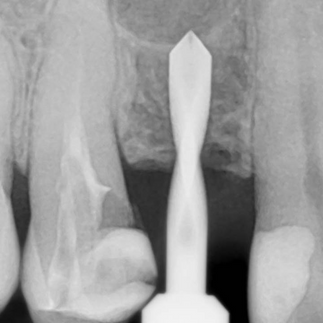

Sinus graft procedure in the crestal approachDr. Pavel YaroshevichMar 10, 20161 min readPre-operative Observation Post-operative observation

Aesthetic Rehabilitation in the Anterior Zone. Implant Placement and Inmediate Loading: Alveolar and Soft Tissue Reconstruction